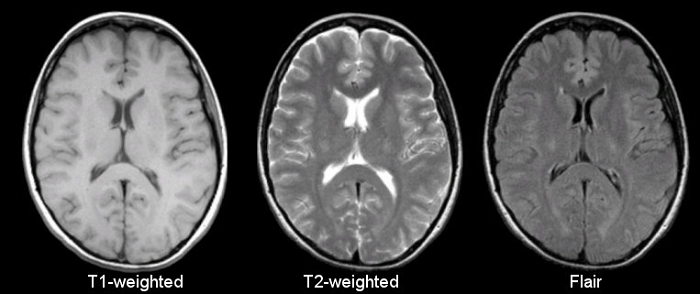

脑医生系统标注的图像

如上图所示,红色的区域是大脑皮层灰质,这个区域的萎缩是阿尔兹海默症患者重要的早期诊断指标。脑医生系统通过自动标注受试者大脑重要结构的体积与正常指标作对比就可以对受试者情况作出判断

王思伦表示,现阶段脑医生最后给出的诊断报告就像我们平时感冒血常规化验单:白细胞总数12.2(正常5-12),中性粒细胞8.6(正常2-7.8),淋巴细胞比例17.9(正常20-40)……诊断报告标包含大脑重要结构的数据,包括脑灰质白质体积,海马结构及全脑45个重要分区的指标,医生一眼就可以看明白,并给出结论。拿到CFDA认证以后,脑医生会推出带有结论的诊断报告,供医生参考